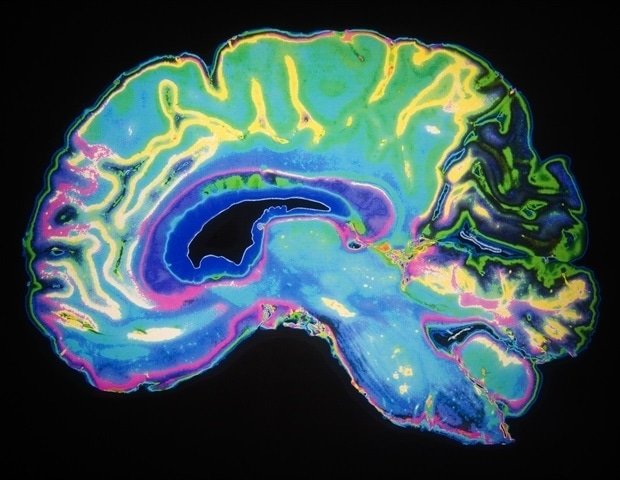

Nerve cells in the brain are constantly bombarded with information from various senses simultaneously. How can the brain prioritize what’s most important?

In a new study published in the journal Nature Communications, researchers at the University of Oslo have revealed that brain cells have a type of volume control function. When you’re focused on a task, you can set certain signals to be amplified over others.

Certain brain cells act as “brakes” to inhibit neural activity. When the mouse focuses on the task of finding its way, VIP cells intervene. They act as “brakes on brakes”.

“By inhibiting cells that are normally quiet, important signals are transmitted with greater intensity,” Vervaeke explains.

“What differentiates this feature from a passive volume control is that it is more like an intelligent amplifier. The VIP cell ensures that important signals picked up in the surroundings are clear and strong while suppressing extraneous background noise.”